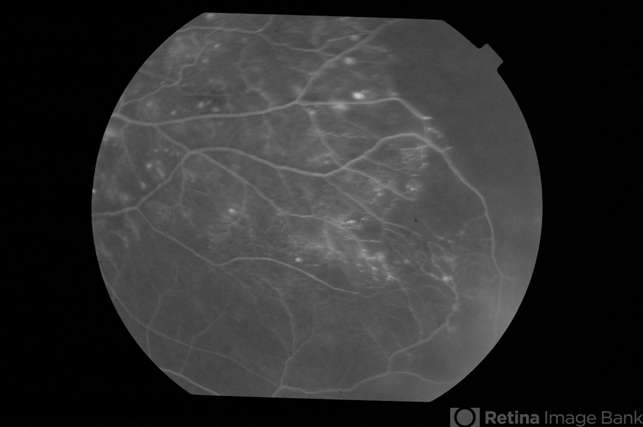

- Adult Coats Disease

- Left fundus of a 61-year-old non diabetic, non hypertensive lady complaining of vision deterioration for 1 year showed massive hard exudates at the macula. Fluorescein angiography revealed microvascular abnormalities over the posterior pole and temporal midperiphery and extensive capillary non-perfusion over the temporal retinal quadrants. OCT revealed macular edema. Fellow eye fundus and angiogram were normal.